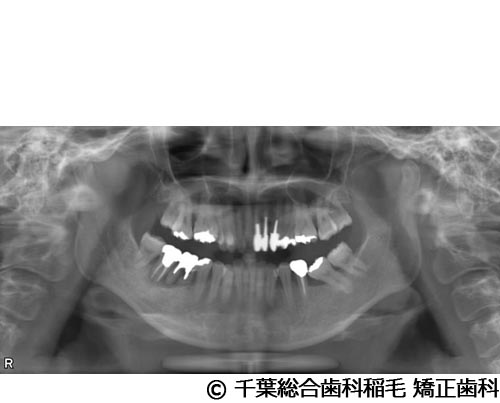

【症例5】All-on-6(オールオン6)

- 治療前

- 治療後

- 治療名

- All-on-6(オールオン6)

- 費用

- 7,500,000円(税込)

- 期間

- 10ヵ月

治療内容

-

患者様の症状

入れ歯が合わなくなり、お食事も満足にできないとご来院されました。

治療法

ご相談の結果、上顎はインプラントを6本、下顎は7本埋入し、All-on-6(オールオン6)という固定式のインプラント治療を行いました。

治療結果

入れ歯が動いてしまう煩わしさがなくなり、よく噛めるようになったと仰っています。

※治療結果は患者様によって個人差があります。